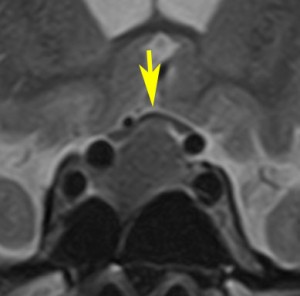

ラトケのう胞はT1強調画像で白く(左:高信号)にみえて,T2強調画像で黒く(右:低信号)にみえることもあります。前の例とはかなり違った印象です。中身は乳白色のドロドロの液体です。矢印のところは視神経交叉(左右の視神経がつながるところ)で,ラトケのう胞に圧迫されて弓形に変形しています。このくらいの視交差の変形では視野障害は出ませんし視力も低下しません。ですから,手術も何もしないで経過観察のみをします。多くの場合は,何も治療しなくて良いものです。この患者さんは無治療で経過を見ました。